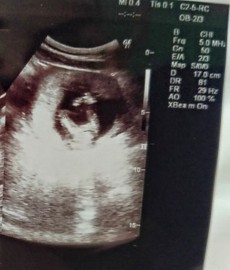

ในรูปภาพคือตอน15+2wค่ะ อยากทราบว่าเห็นเพศหรือยังคะ พอดีหนูท้องแรกดูไม่เป็นเลยแถมหมอไม่ได้แจ้งอะไรด้วย ขอบคุณล่วงหน้านะคะ ❤️

ในรูปไปทางผู้หญิงค่ะ แต่แค่ 15W ยังไม่ชัดเจน ซาวด์อีกสัก 2 รอบยืนยันก็น่าจะ 100% สัก 20W